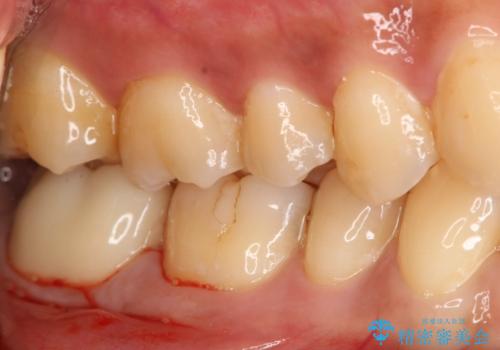

- 過去に他院で治療した部位が材料劣化を起こしていたため、セラミック治療を希望された患者様です。

切削量を考慮し、セラミックインレーを選択しました。

虫歯が深かったので、CRを詰めた上で形態を整えています。